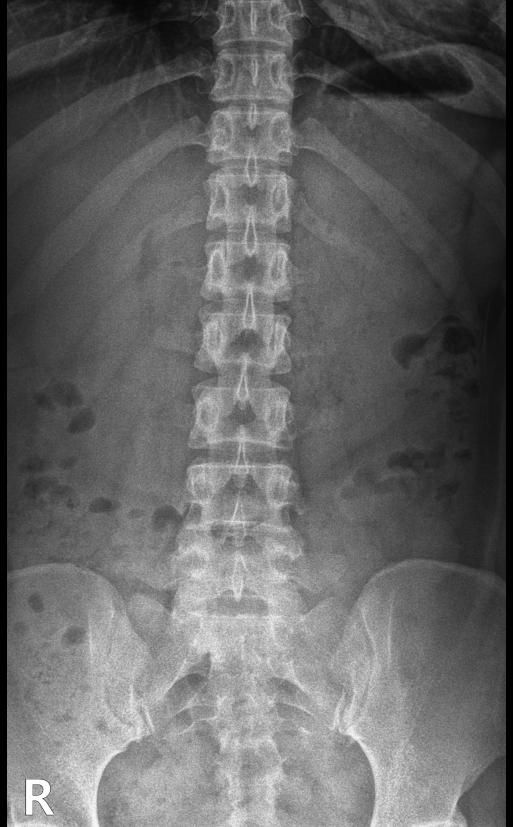

척추분리증인가요??(엑스레이 있어요)

한 병원에서는 척추분리증이라고 하고 한 병원에서는 척추분리증이 아니라고 해서요. 혹시 아래 사진에서 척추분리증 소견이 보이는 사진이 있나요??

여기까지가 a병원에서 찍은 사진이고 아래가 b병원에서 찍은 사진이에요!

척추분리증 맞습니다.

A병원 세번째 사진의 아래 부위에 척추분리증이 있는게 맞습니다.

B병원 사진에서는 비교적 흐리게 보이지만 잘 보면 B병원 엑스레이에서도 같은 부위에 분리증을 확인할 수 있습니다.

두 사진을 비교해서 보았을 때 큰 문제가 있어 보이지는 않으며 엑스레이상 척추분리증 진단이 어렵거나 애매한 경우에는 추가적인 검사 MRI를 통해 진단을 받아보시는 것도 방법이라고 생각합니다.

제가볼때 엑스레이상에 분리증은 보이지않지만 각도에따라 그리고 기계에따라서 달라질수있으니 정확하게 하고싶다면 MRI검사를 추천합니다 감사합니다~

두가지 사진을 비교해보았을 때, 크게 특징적인 것이 관찰되지는 않습니다. 척추분리증을 진단하는 것은 임상증상과 영상검사를 통한 구조적 이상을 확인하는데요, 정확한 검진을 위해서는 ct나 mri같은 검사를 고려하시거나, 척추질환을 전문적으로 진단하는 병원급 의료기관에 방문해보시는 것도 고려해보시면 좋겠습니다.